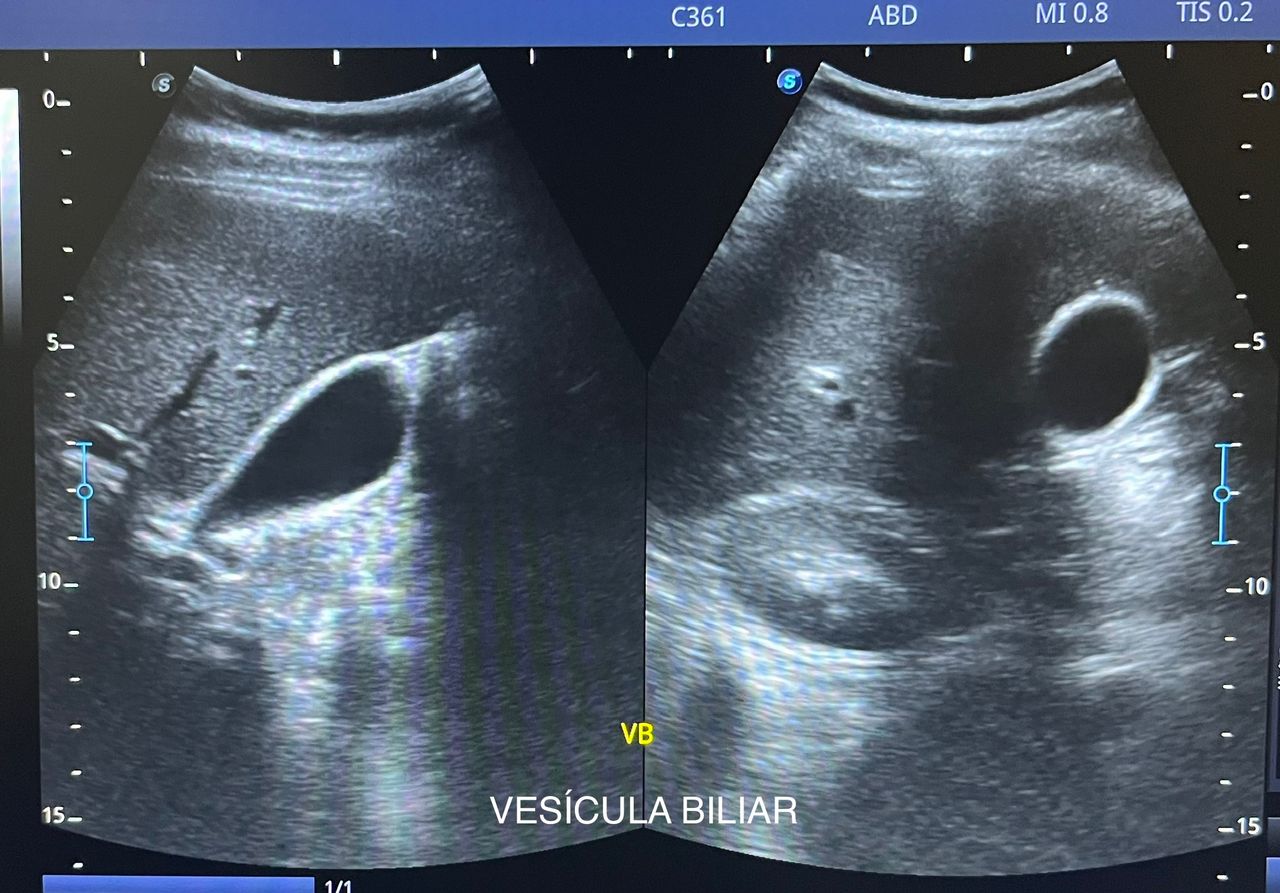

Médico general con 15 años de experiencia, master en enfermedades infecciosas y antibioticoterapia por parte de la Universidad Cardenal Herrera en Valencia, ademas de diversos diplomados en el área de Infectología y Parasitología, Urgencias, Imagenología y Medicina del Trabajo. He laborado en Hospitales y Clínicas en el área de Urgencias, en Laboratorios realizando estudios de Imagen, en especifico ultrasonidos de todo tipo desde básicos hasta avanzados incluidos los obstétricos estructurales, en Secretaría de Salud del Estado de Querétaro realizando ultrasonidos obstétricos para la detección de malformaciones en los tres trimestres del embarazo en diversos centros de salud, como médico de Empresas en el campo de Salud Laboral y actualmente en este consultorio en donde para su mejor atención y siempre buscando integrar la mayoría de las herramientas diagnosticas cuento con equipo de ultrasonido como apoyo en la exploración del paciente o como servicio diagnostico por imagen, realizo ultrasonidos convencionales (hepatobiliar (hígado, páncreas, vesícula y bazo), vías urinarias, ginecológico abdominal y transvaginal, tiroideo, prostático, testicular, pared abdominal) y especializados (dopler obstétrico en los 3 trimestres de embarazo), musculoesquelético en lesiones deportivas. También cuento con un equipo de electrocardiograma de 12 derivaciones para monitoreo completo del funcionamiento cardiaco, espirometria para evaluar la función pulmonar en la consulta, pruebas rápidas que se realizan en consultorio para detectar de forma mas precisa enfermedades infecciosas como Influenza A y B, covid19, infecciones urinarias, dengue, zika, chikungunya. Cuento con diversas vacunas para prevención de enfermedades. Siempre con el objetivo de dar el mejor servicio y atención a su salud. Lo espero en consulta para escucharlo y estudiar su caso de la forma más completa posible, estoy seguro de que tendremos las mejores opciones para su tratamiento. Mi tranquilidad es que usted se vaya con todas sus preguntas e inquietudes resueltas.

• Ultrasonido hepatobiliar

$800